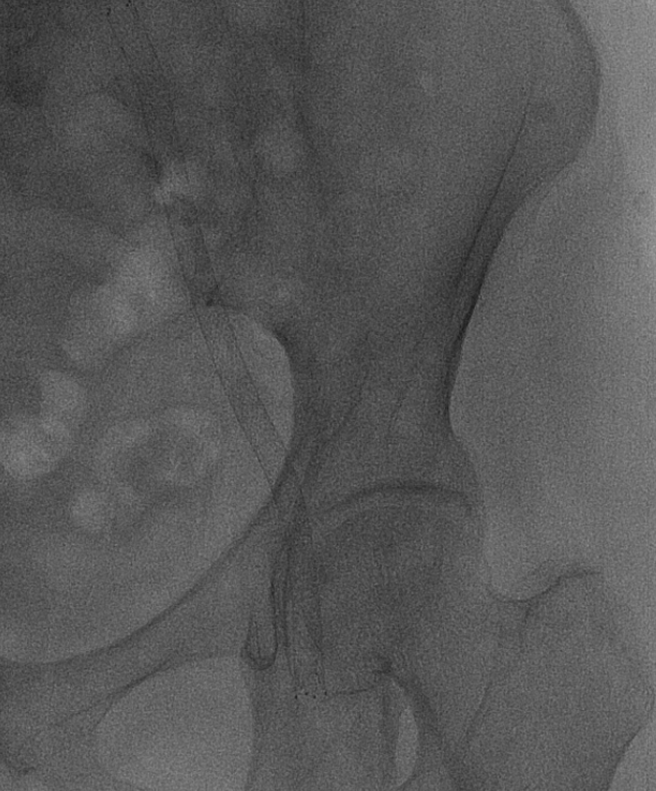

术中资料

当地医院左侧髂动脉支架远端跨关节,至股浅动脉。

造影显示右侧髂外动脉、股动脉血栓栓塞。